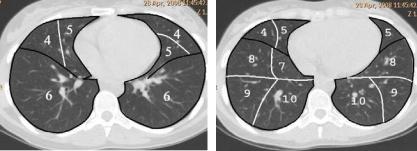

вену. В верхней доле правого легкого 3 сегмента, средней доле правого легкого 2 сегмента и нижней доле правого легкого 5 сегментов. В верхней доле левого легкого 5 сегментов, в нижней доле левого легкого 4 сегмента. Сегментам присвоены номера от 1-го до 10-го. В левом легком отсутствует 7-й сегмент за счет наличия сердечной вырезки. Четкое сегментарное строение легких визуализируется при КТ (рис. 22).

Рис. 22. Бронхолегочные сегменты при компьютерной томографии